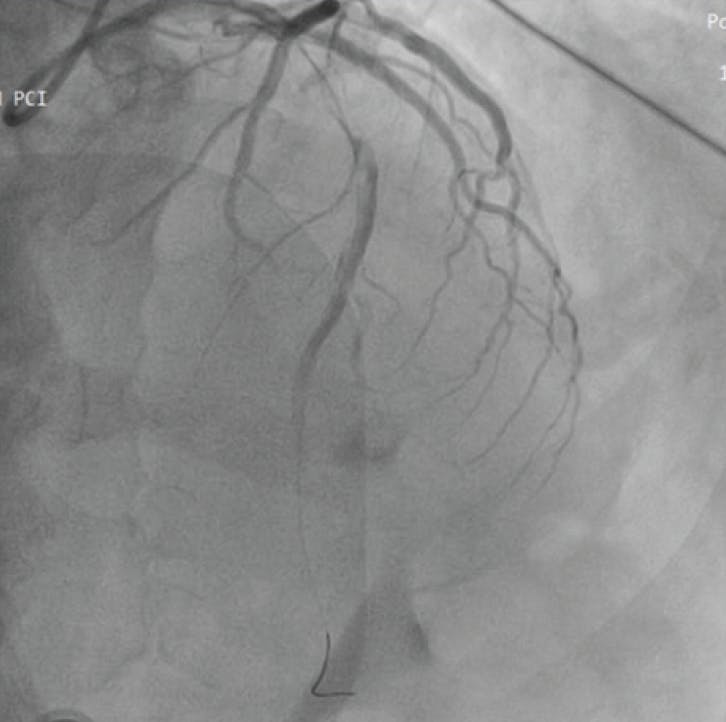

INTERVENTION

Three CAT RX passes were performed from proximal to distal, with aspiration continuously on as the catheter was advanced in a slow, controlled manner. Angiography after CAT RX showed an optimal thrombus resolution and lesion visualization. A stent was then placed, resulting in final TIMI III flow with preservation of all side branches (Figure 3). At the end of the procedure, we retrieved a massive 3.5-cm-long thrombus from the Penumbra canister (Figure 4).

Figure 3. Angiographic view (cranial 40°) showing final TIMI III flow after CAT-RX and stenting in the LAD.

The patient had a decent recovery, a 7-day hospital stay, and a left ventricle ejection fraction (LVEF) of 45%, with akinesia of the medial and distal anterior wall at discharge. At 3-month follow-up, the patient was in a stable clinical condition.

DISCUSSION

The use of the Penumbra device was key for the successful treatment of this anterior STEMI. Due to its aspiration capabilities, we were able to better restore coronary flow in a short time. The final angiographic result was perfect and even if we achieved only 45% of LVEF after the procedure, the patient was stable at 3-month follow up. Suboptimal LVEF after anterior STEMI is related to different procedural and clinical factors that are still under investigation even after several years of primary PCI experience.